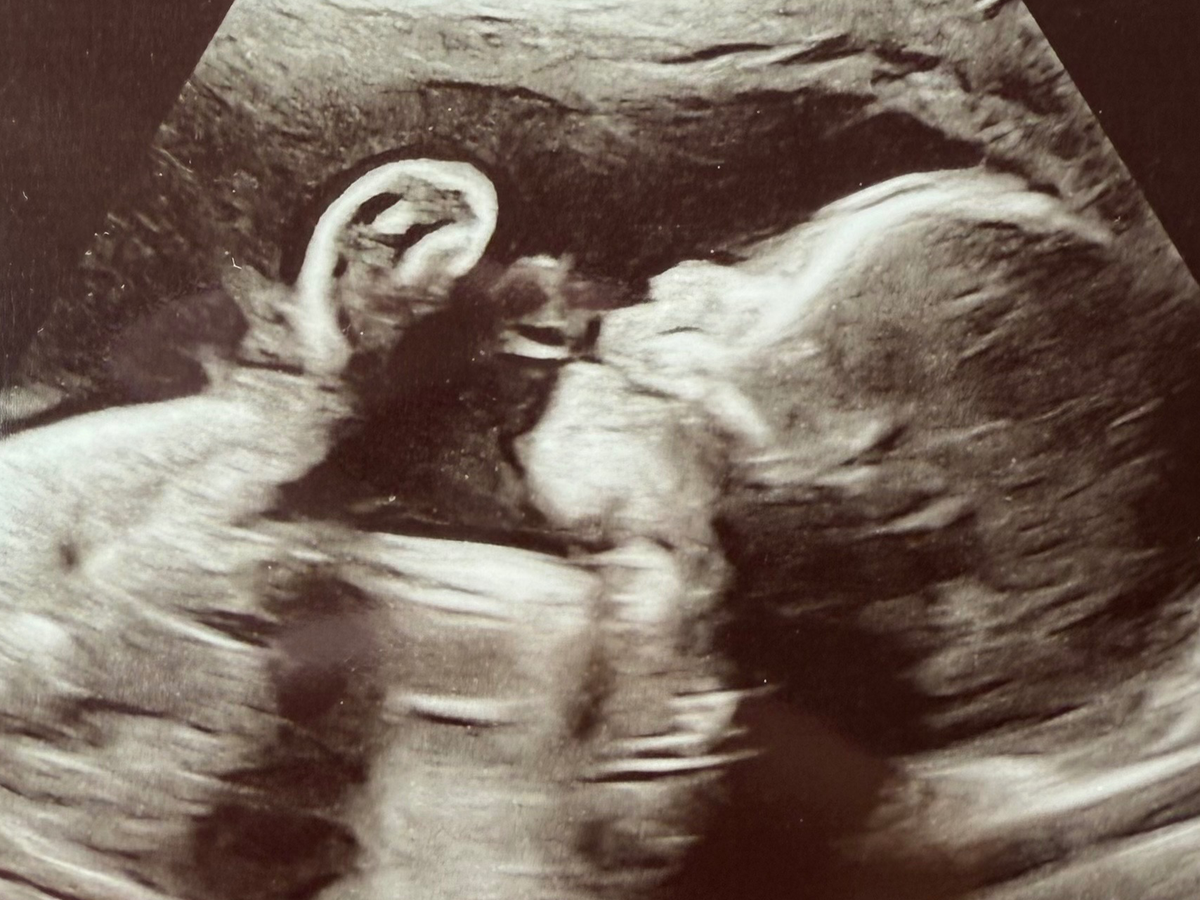

She and her husband, Edgar, are expecting their first child, sweet baby girl, Valentina. She is already so deeply loved, and we are trusting for strength, healing, and provision every step of the way. I created this GoFundMe to support them as they prepare for the medical care, surgeries, and unknowns ahead.

Valentina has been diagnosed with several complex congenital heart and organ conditions. She has Hypoplastic Right Heart Syndrome (HRHS), meaning the right side of her heart is underdeveloped. She also has Double Outlet Right Ventricle (DORV), where both major arteries come from the right side of her heart instead of being properly separated.

In addition, Valentina has Pulmonary Stenosis (PS), which means the pathway to her lungs is very narrow, making it harder for blood to flow properly.

She has also been diagnosed with heterotaxy syndrome, a condition that affects how her organs are arranged. Her stomach is on the right side, her liver sits in the middle, her intestines are rotated, and she does not have a spleen, which can affect her immune system.

Because of these conditions, Valentina will need at least two major heart surgeries, one around 3 months old and another around 3 years old, to help correct the “plumbing” of her heart and improve how it functions.

Immediately after birth, she will be transferred to the pediatric cardiac care unit at Children’s Hospital. There, doctors will perform genetic testing, an MRI, and evaluate whether her pulmonary veins are properly connected to her heart. Depending on what they find, she may need emergency surgery right after birth.